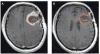

The current method for assessing the response to therapy of glial tumors was described by Macdonald et al. in 1990. Under this paradigm, response categorization is determined on the basis of changes in the cross-sectional area of a tumor on neuroimaging, coupled with clinical assessment of neurological status and corticosteroid utilization. These categories of response have certain limitations; for example, cross-sectional assessment is not as accurate as volumetric assessment, which is now feasible. Disentangling antitumor effects of therapies from their effects on blood-brain barrier permeability can be challenging. The use of insufficient response criteria might be overestimating the true benefits of drugs in early-stage studies, and, therefore, such therapies could mistakenly move forward into later phases, only to result in disappointment when overall survival is measured. We propose that studies report both radiographic and clinical response rates, use volumetric rather than cross-sectional area to measure lesion size, and incorporate findings from mechanistic imaging and blood biomarker studies more frequently, and also suggest that investigators recognize the limitations of imaging biomarkers as surrogate end points.